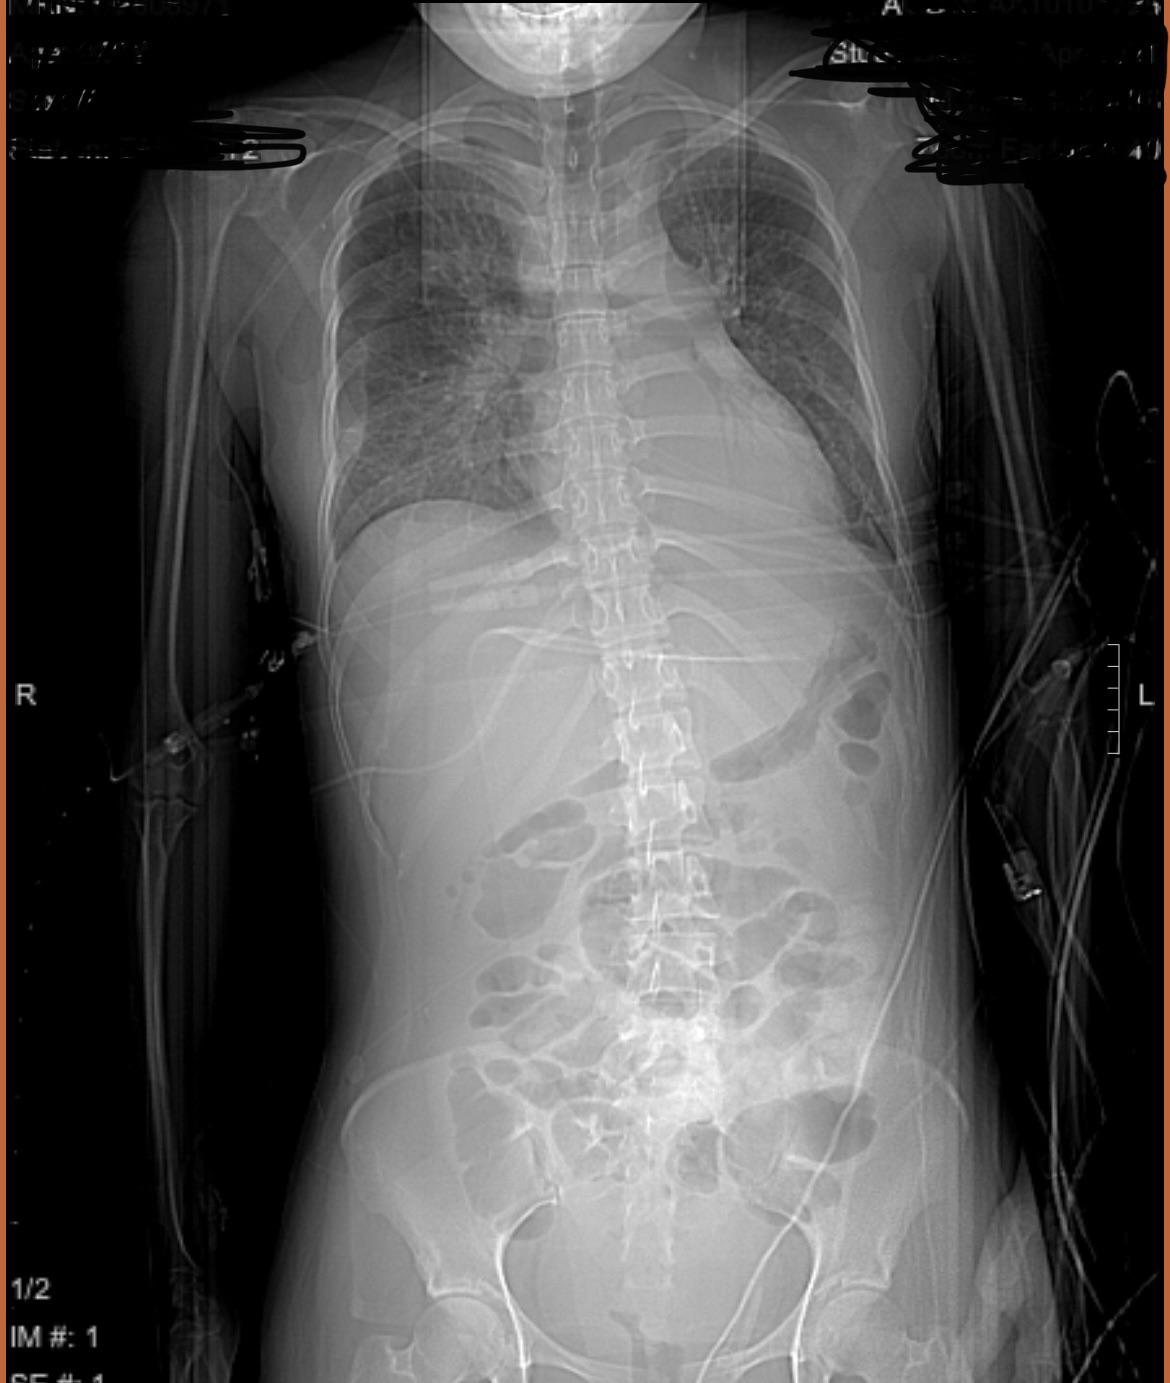

Mild scoliosis causing lateral pelvic tilt to the right? r/scoliosis Does Lateral Pelvic Tilt Cause Pain A lateral pelvic tilt may cause the sacrum to be positioned asymmetrically in relation to the ilia, or “wings,” of the pelvic girdle, which may cause sacroiliac joint pain. When the ql is tight, more often on the right side (in the left aic pattern, our bodyweight is shifted to the right), it can contribute to abnormal pelvic mechanics (and. Does Lateral Pelvic Tilt Cause Pain.